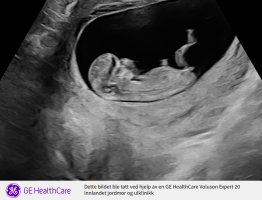

Vis vedlegget 456730